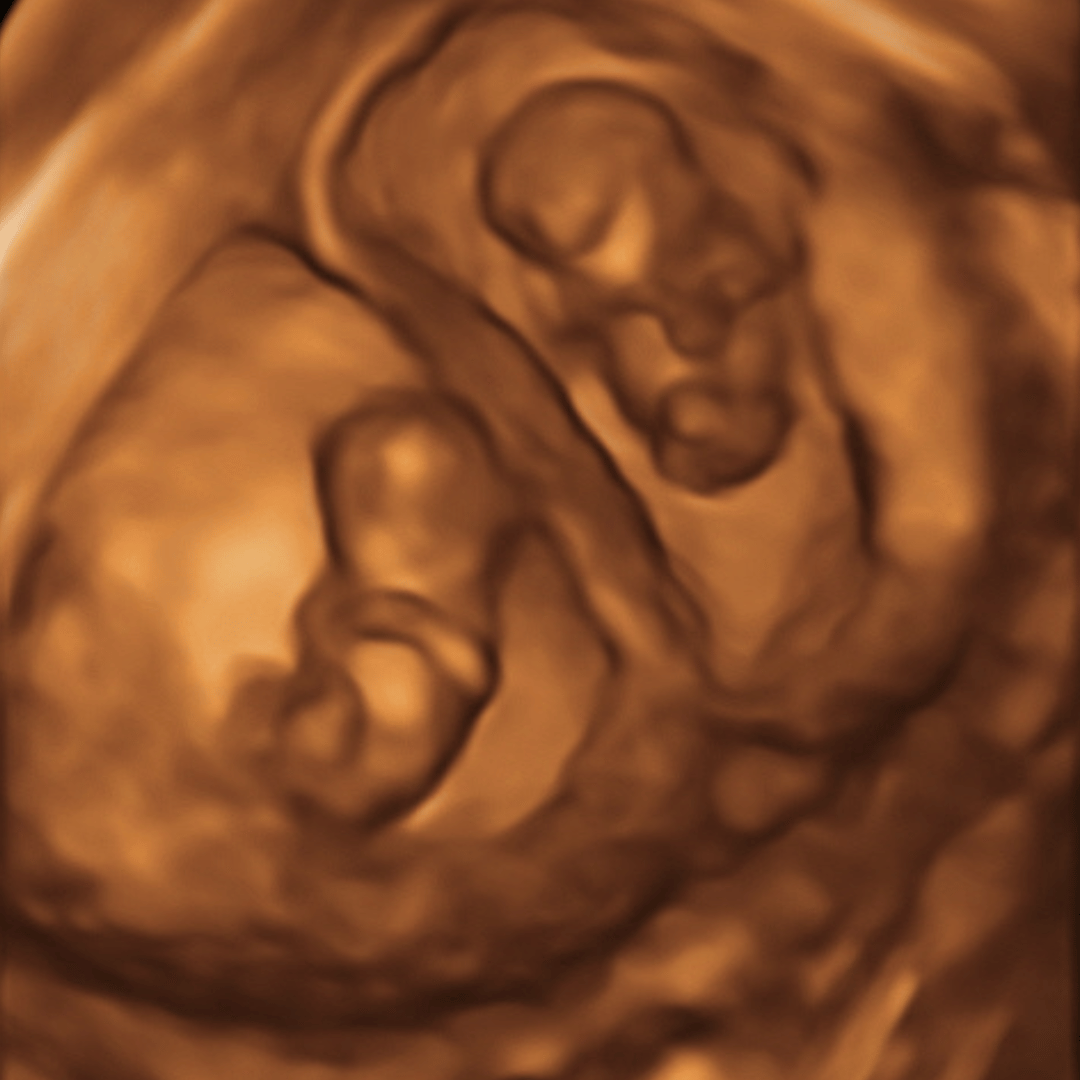

6 To 13 Week Ultrasounds

Quick Peek

9-13 weeks – $60

- Same as Peace of Mind package, and includes a quick peek of baby in 4D